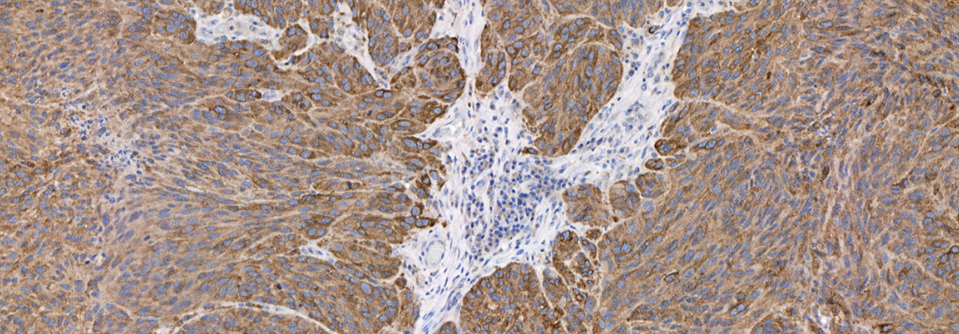

• Sharp & Well-Defined Staining

• Multiplex Protocols

NeoPATH Pro sets a new standard in automated advanced staining for IHC, ISH, and FISH. Designed to meet your laboratory’s current staining needs while adapting to future demands, this advanced staining platform delivers high-capacity throughput, optimized reagents, and intuitive automation. Innovative features such as independent slide positions, integrated slide scanning, and Al assisted error prevention streamline workflows and enhance diagnostic confidence.